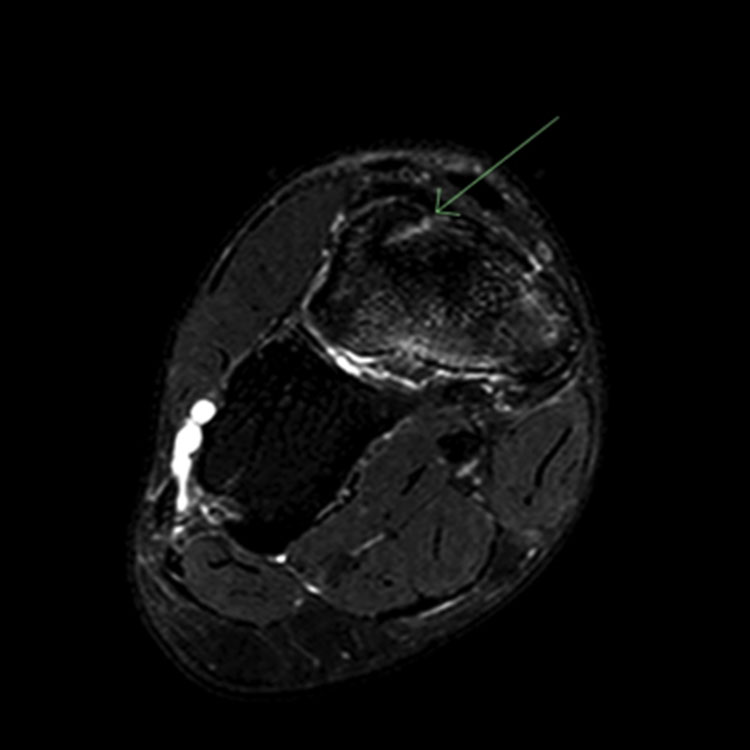

1. Accurate giagnosis 정확한 진단 : 피로반응이나 골절을 정확하게 진단하는 것이 효과적인 관리의 가장 중요한 요소.

내측 복사뼈 (Medial malleolus): 본질적으로 불안정하고 비유합되기 쉬우므로 고위험 피로골절로 간주됩니다. X-ray나 CT에서 골절선이 보이지 않는 경우 4~6주 동안 적극적인 고정(엄격한 비체중 부하)이 필요합니다. 골절선이 명확한 경우 **개방 정복 및 내고정술(ORIF)**이 선택 치료입니다.